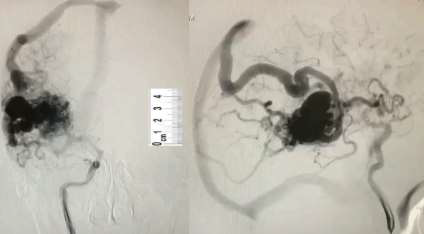

O paciente da questão anterior realizou uma angiografia.

Fonte da Imagem: cedida pelo autor

De acordo com o achado dessa imagem, assinale a alternativa CORRETA.